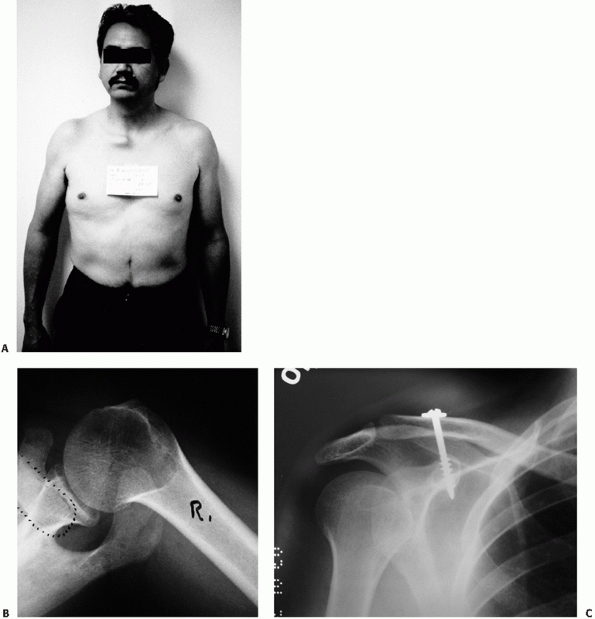

![]() |

FIGURE 40-4 Dislocation of both ends of the clavicle. A. Clinical view demonstrating anterior dislocation of the right SC joint. B. The axillary radiograph reveals posterior dislocation of the AC joint. C. These injuries are generally treated by AC joint repair/reconstruction with return of near normal function.